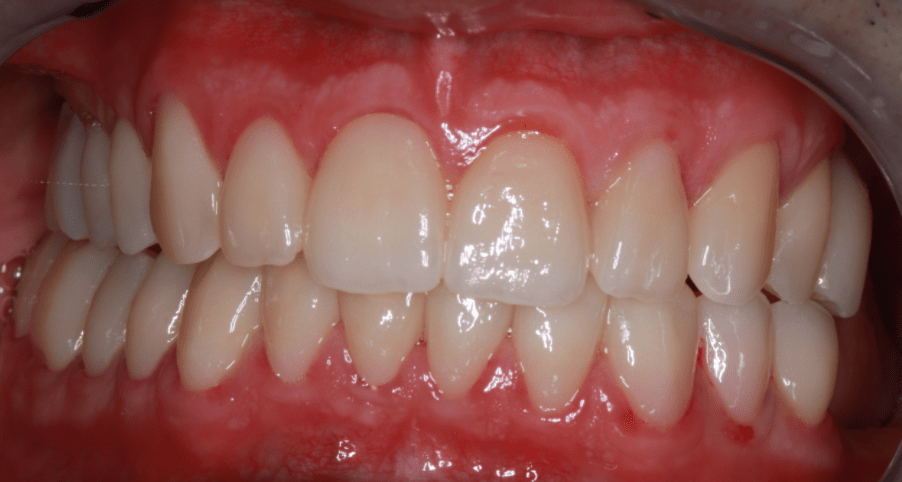

Klinikai és radiológiai vizsgálatok alapján megállapítottam, hogy a túlterhelés (parafunkciók) jelei látszódnak a fogain is: abfrakciók – nyaki kopások és attríciók –, rágófelszíni kopások is kifejezettek voltak. Harapása igen bizonytalan tartományban mozgott, nem volt egy stabil helyzet, amelybe határozottan össze tudott volna zárni (csak kereste a megfelelő pozíciót.) TMI-vizsgálat során reciprok crepitációt (kattanás nyitáskor-záráskor is), myofascialis eltéréseket (hypertrófiás musculus masseter – túlterhelt rágóizom) és beszűkült mozgáspályákat találtam. Emellett sajnos a nem megfelelő szájhigiénés szokások miatt a fognyakak „sérült” részein szuvasodások is megjelentek, illetve a bal alsó hatos és a jobb felső hetes fog már oly mértékben destruálódott, hogy el kellett távolítani őket.

A nagy kiterjedésű szuvasodások ellátására, továbbá a harapási forma és ezzel együtt az ízületi panaszok megszüntetésére full kontúr cirkón pótlást terveztem, melyet individuálisan a rendelőnk ARCUSdigma készülékének segítségével készítettem el.

Miután a pácienssel megbizonyosodtunk a pótlás funkcionalitásának sikerességéről, készre kértük a fogtechnikai laborból azt a cirkóniumpótlást, amely a kisebb korrekciókon átesett ideiglenes pótlás tökéletesen pontos mása lett.

A páciens az elért eredménnyel mind funkcionálisan, mind esztétikailag azóta is maximálisan elégedett.